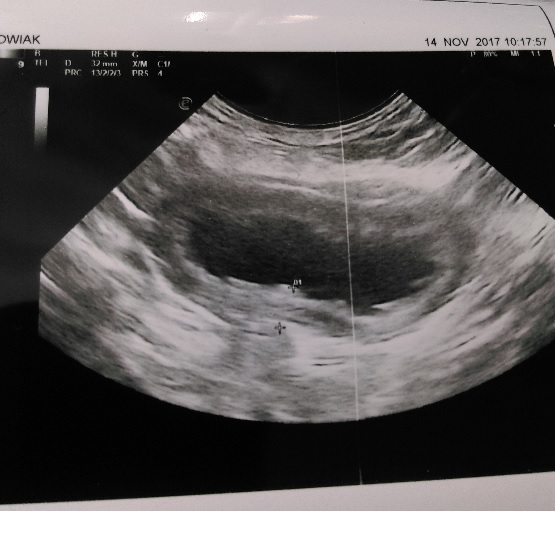

14.11.17r. - Udałam się do jeszcze innego weterynarza. Tu na miejscu zrobiła USG i morfologię z biochemią. Podczas robienia USG Pani weterynarz wykluczyła ropomacicze, ale okazało się, że sunia ma bardzo poważne zapalenie pęcherza moczowego, co potwierdziły wyniki badań. Niestety przez to iż wczoraj miała podany jak się okazało steryd, wyniki mogą być przekłamane i badania trzeba powtórzyć. - ta wizyta 105zł